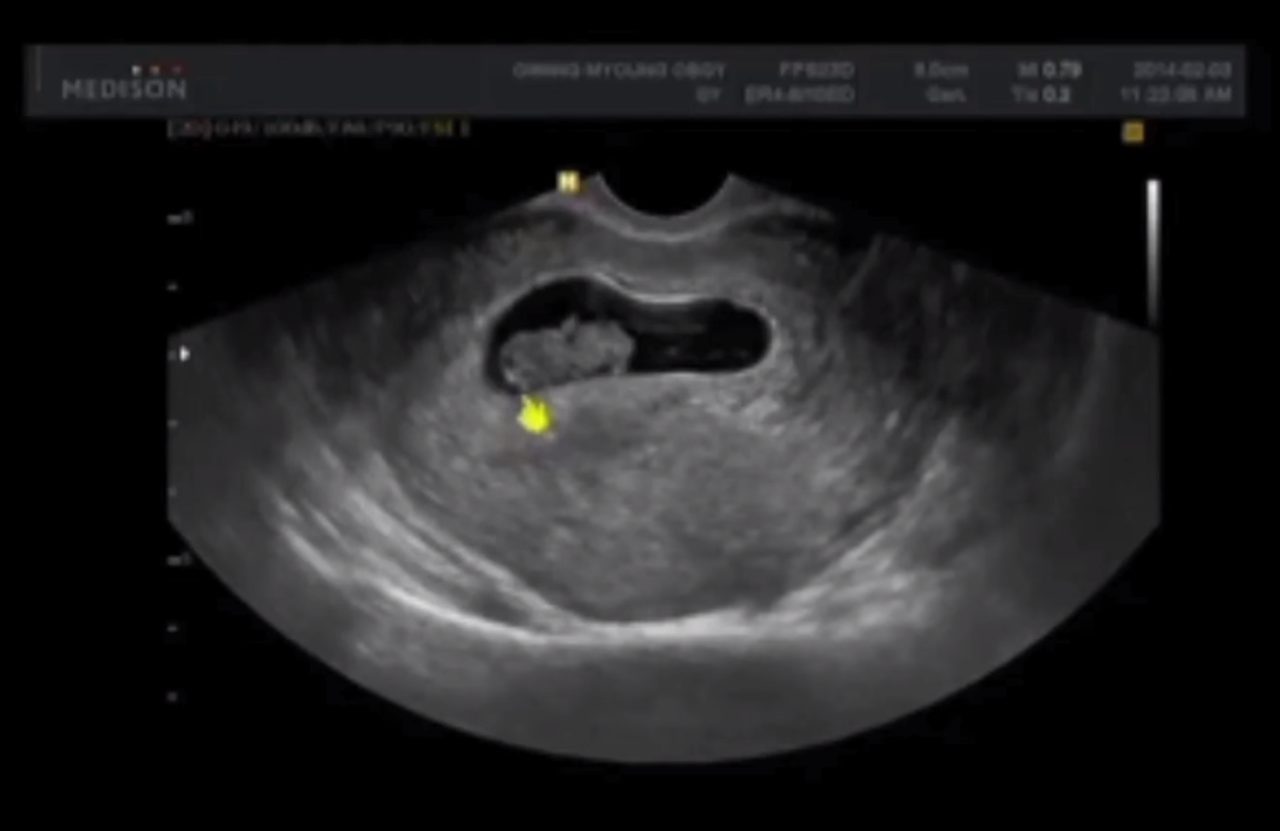

하지만 이미 나는 초음파를 통해 아이의 심장소리를 들었고, 젤리곰 같이 동그란 두손, 두 발이 달린 아이의 모습을 내 두 눈으로 똑똑히 봤고, 내가 내린 결정을 뒤엎을 수 없는 어쩔 수 없는 엄마가 되어 있었다.